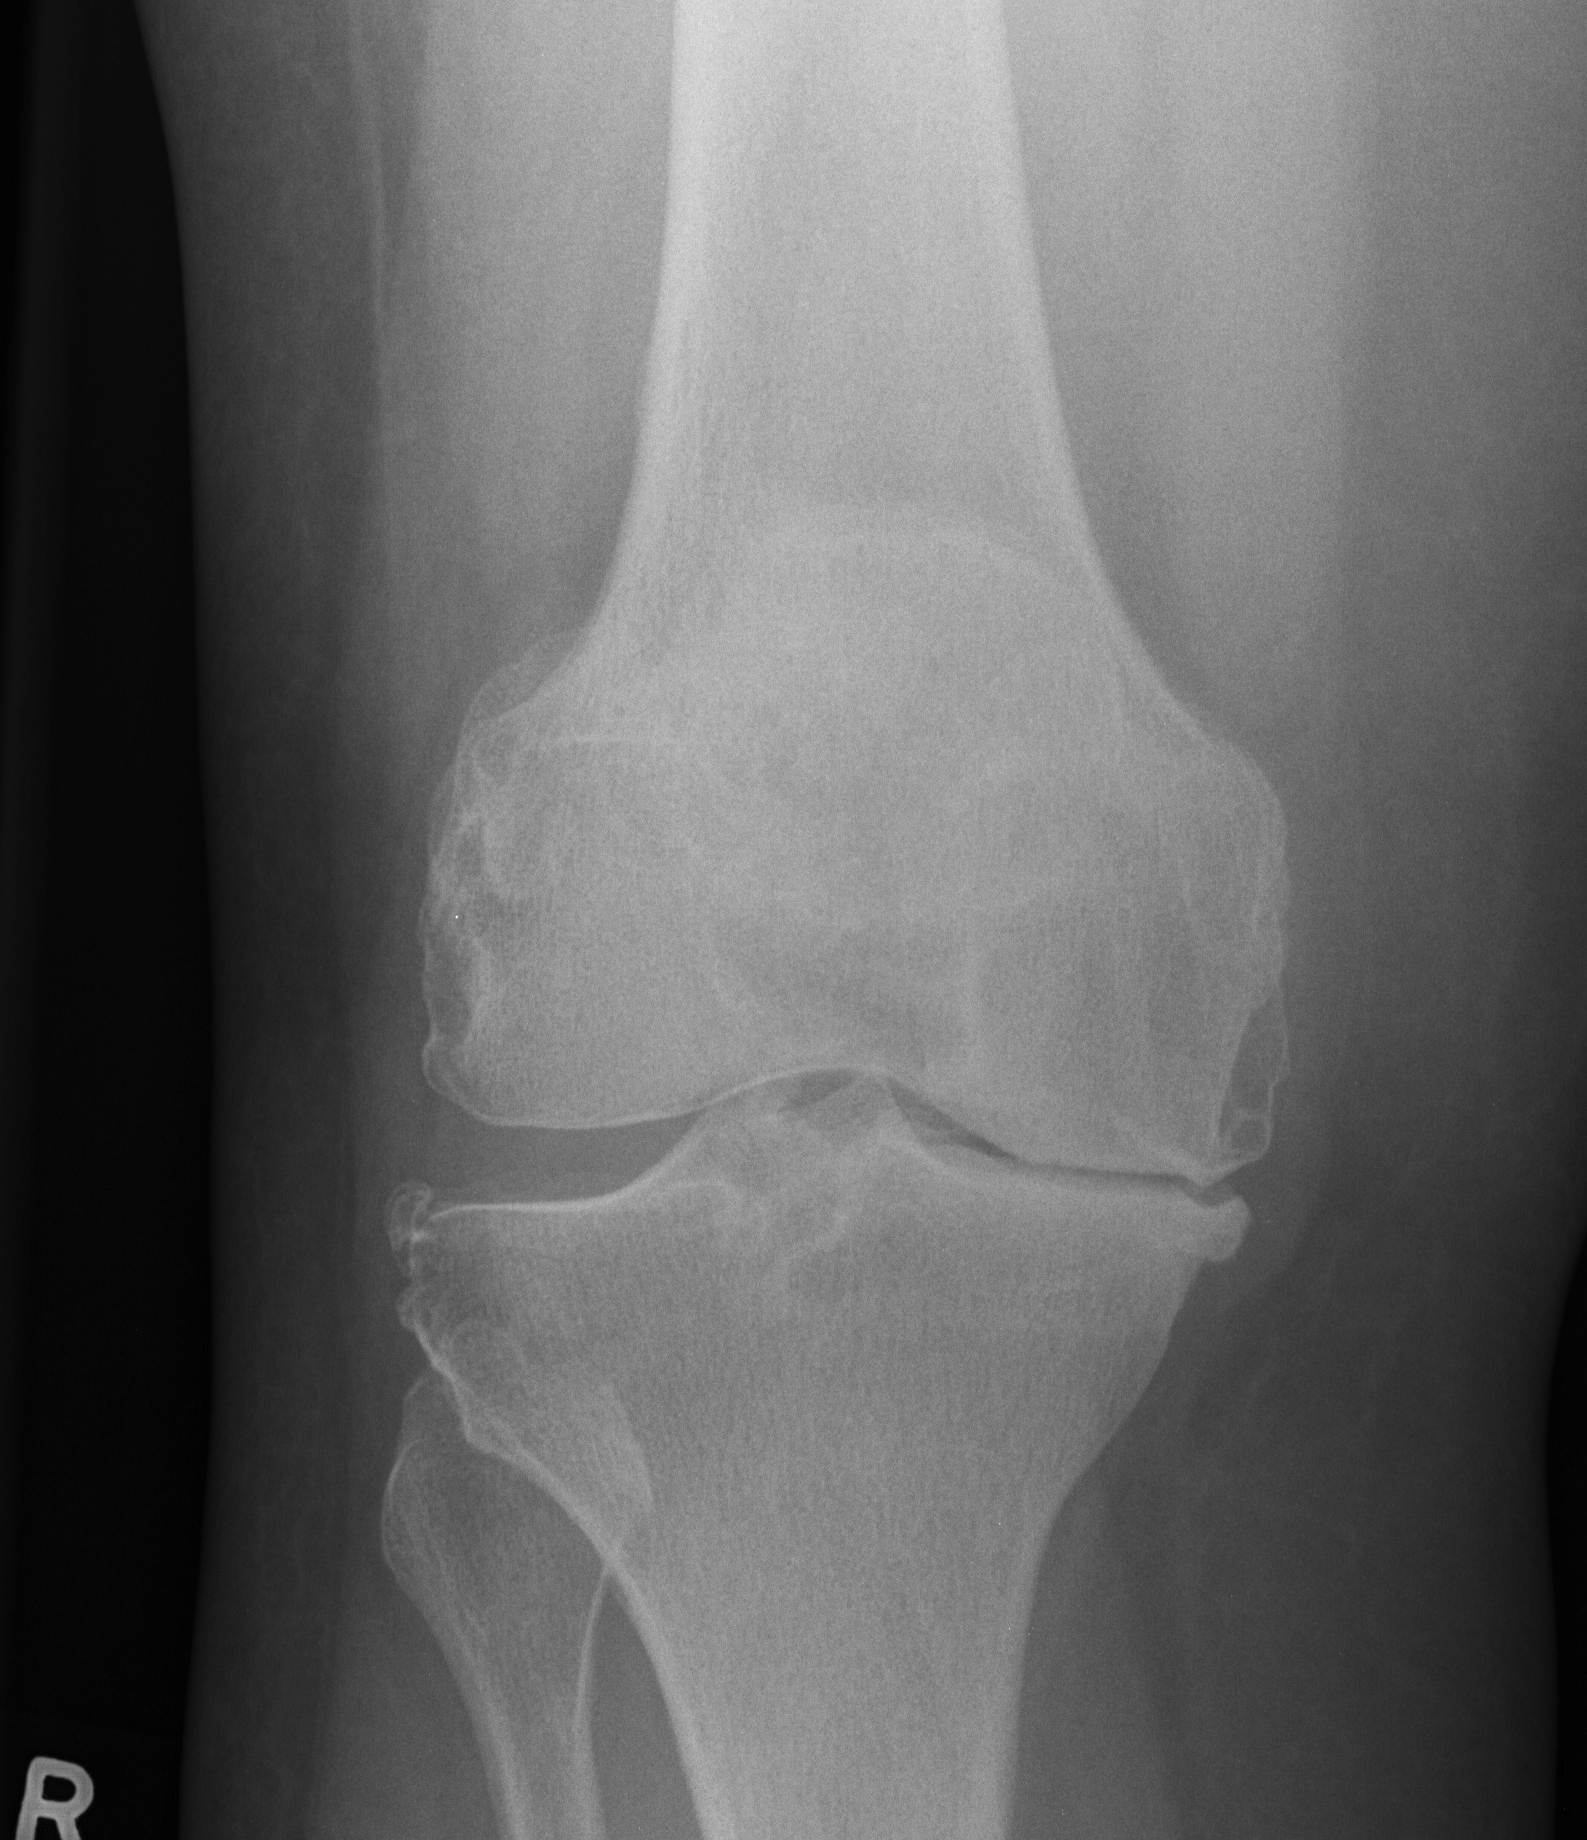

Xray

Full length standing AP X-rays

- calculate valgus cut angle

- difference between MAF and AAF

- allows assessment of any femoral or tibial deformity

AP and lateral x-rays

- template femoral and tibial implant sizes

Lateral xray

- look for patella baja (may make exposure difficult)

Evaluate deformity

- need for constraint

- need for augments

- need for stems